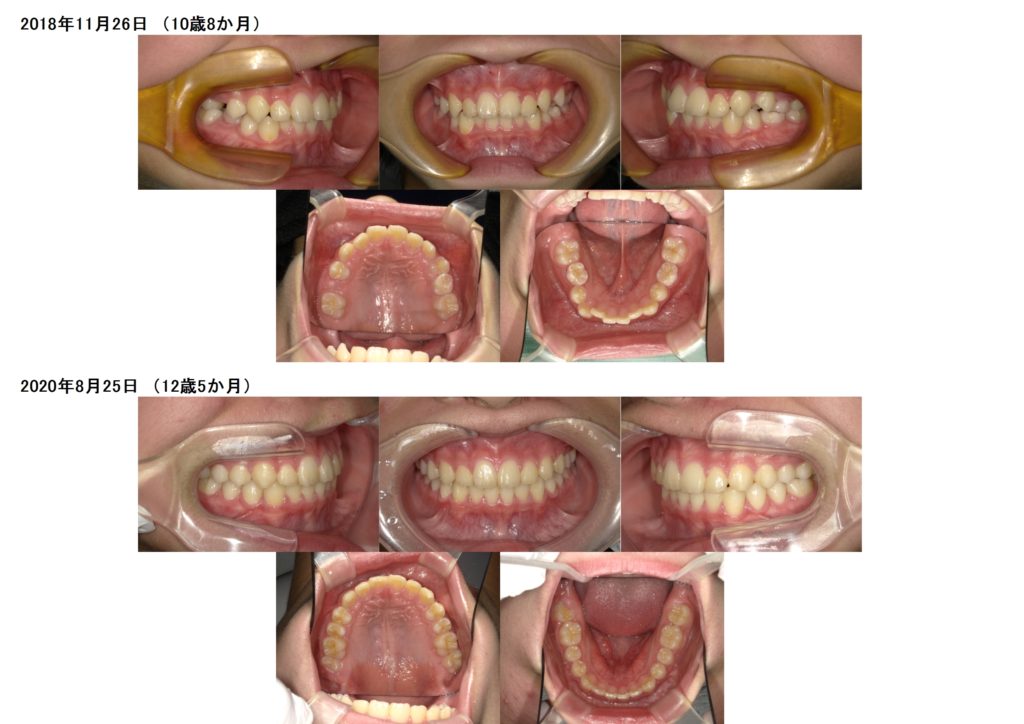

↑10歳8か月で来院された患者様ですが、ほぼ永久歯が生えそろっている状態です。

上下のスペースが不足しているので、残された成長を利用して上下の顎を広げる装置を入れ広げた状態です。

↑その後、スペースが確保でき上下フルブラケット装置を着けました。

↑治療前、治療後の写真です。

2年かからず、上下の顎を広げ、フルブラケットで治療が終わりました☆